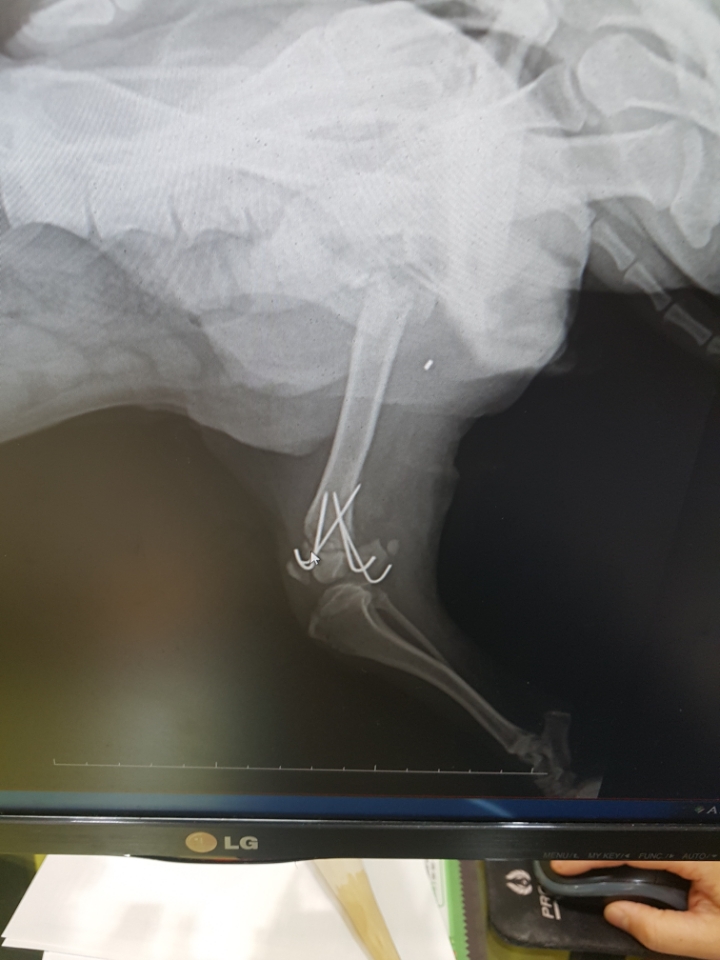

수술후 일주일이 되어서 엑스레이 찍고 왔습니다

아직 수술부위에 가골이 차지않아 조심해야한다고 하세요

다리를 전혀 디디려하지 않아 고관절 운동을 열심히 해주라고 하시네요